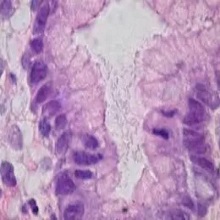

| Гастритис спада у групу најчешћих обољења гастроинтестиналног система, а представља упални процес слузокоже желуца. Слузокожа облаже желудац и има важну улогу у процесу варења и стварању желудачне киселине, помоћу које се храна у желуцу разграђује. Осим хране, желудачна киселина има и заштитну улогу, јер штити организам од различитих патогених микроорганизама које унесемо у себе. |

| Гастритис је хистолошки доказана инфламација слузокоже желуца. Дели се на акутни и хронични гастритис. Етиолошка подела гастритисе дели на инфективне и неинфективне. Откриће Хеликобактер пилори инфекције потпуно је променило поглед на етиологију гастритиса. Данас се зна да је најчешћи узрочник (у преко 90% случајева) инфективног гастритиса Хеликобактер пилори, а потом Хеликобактер хеилмани и ентеровируси. |

Хронични гастритис представља запаљење желудачне слузнице коју карактерише лимфоплазмацитама инфилтрација. Ово обољењеје често локализовано и неправилно распоређено дуж желудачне слузокоже. |